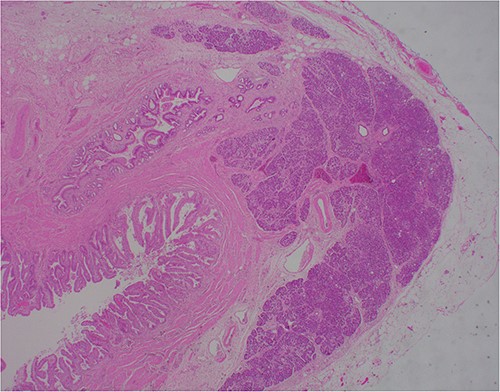

At outpatient phone clinic review 2 months post-surgery, the patient had recovered well, and his pre-operative symptoms of nausea, vomiting and pain had completely resolved. The histopathology of the gallbladder found chronic cholecystitis with cholelithiasis, in addition to a 6 mm focus of pancreatic heterotopia in the gallbladder wall. This heterotopic tissue contained acini, ducts and islet cells, classifying it as Type I pancreatic heterotopia (Figs 1–3).

×10 objective lens; showing central duct with surrounding pancreatic acini and islets, with preserved architecture.